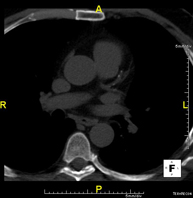

Prueba diagnóstica que consiste en obtener imágenes del tórax de alta definición anatómica (pulmones, corazón, mediastino, grandes vasos, caja torácica, etc.) mediante el empleo de un equipo de TC (Tomografía Computarizada). Dichas imágenes se estudian posteriormente en una estación de trabajo que permite reconstrucciones bidimendionales en diferentes planos del espacio y también reconstrucciones 3D (volumétricas). Algunos estudios requieren el empleo de contraste yodado para mejorar la definición de las imágenes. - Angio-TC Aorta torácica